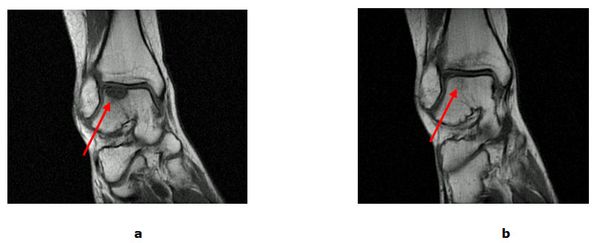

Bei isolierten Knorpel/Knochen Verletzungen (Osteochondrale Läsion, Osteochondrosis dissecans) kann während einer Gelenkspiegelung eine vitalisierende Anbohrung des Knochens erfolgen. Besteht bereits ein ausgeprägter Knorpelschaden wird mit einem speziellen Instrumentarium die harte Knochenschicht durchbrochen und die Bildung von Ersatzknorpel angeregt (Mikrofrakturierung). Der freie Gelenkkörper wird vorher entfernt. Dauerhaft schmerzhafte umschriebene Knorpelläsionen können durch die Verpflanzung eines Knorpel-Knochen-Zylinder (Mosaikplastik, Knorpel-Knochen-Zylinder Transplantation) therapiert werden. Aus einem gesunden nicht belasteten Gelenkanteil wird ein Knorpel-Knochen Zylinder entnommen und in der sog. „Press fit“ Technik am Sprungbein eingesetzt. Ein anderes Verfahren, die sog. MACT eignet sich zur Therapie großer Defektzonen. Bei der MACT (Matrix gekoppelte Autologe Chondrozyten Transplantation) wird Knorpel entnommen und an ein Speziallabor geschickt. Die entscheidenden Zellen werden isoliert, vermehrt und in einer Zweitoperation auf den Knorpeldefekt aufgebracht.

Abb.3: a Gelenkspiegelung mit freiem Gelenkkörper im oberen Sprunggelenk (OSG). b Mikrofrakturierung eines Knorpelulcus am Sprungbein.

Abb.4: a MRT (Kernspintomografie) vor der Mikrofrakturierung mit Knorpel-Knochen Schaden (Pfeil). b 8 Monate nach erfolgter Therapie mit revitalisiertem Gewebe (Pfeil).